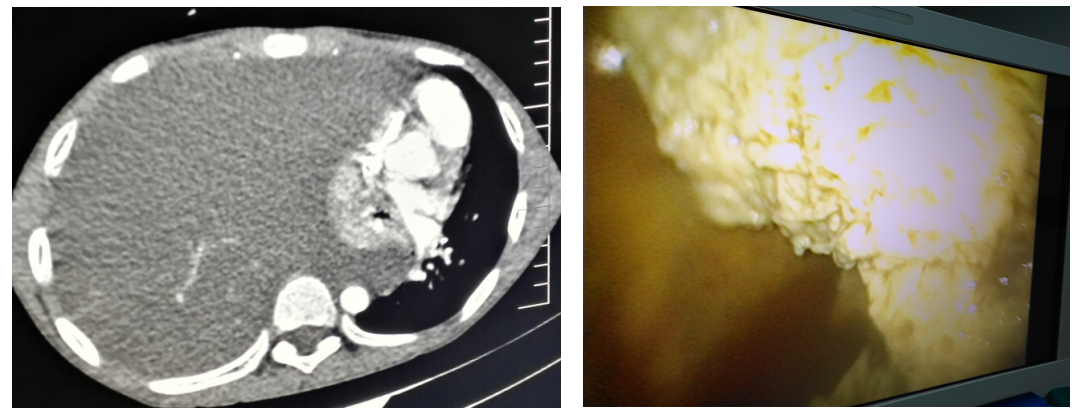

3. 电视胸腔镜微创治疗肺吸虫性脓胸

2. 肺吸虫感染性胸膜炎